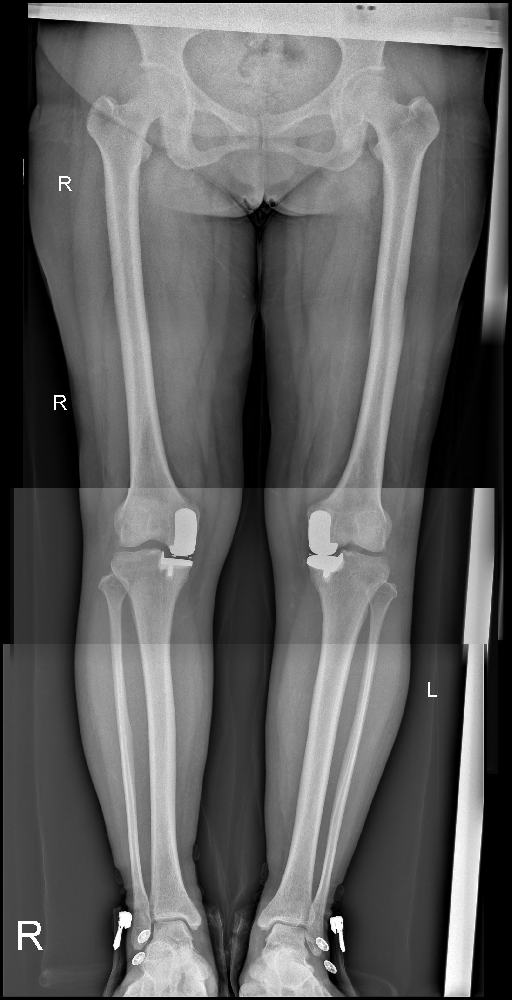

李娜,一個(gè)45歲的女性,居住在市中區(qū)齊村鎮(zhèn)尖山子村。她因?yàn)殡p膝間斷疼痛已有8年之久,最近終于決定入院治療。患者自述癥狀發(fā)生在8年前,當(dāng)時(shí)并沒(méi)有明顯的誘因,雙膝開(kāi)始出現(xiàn)疼痛。這種疼痛是間斷性的,勞累后疼痛會(huì)加重,但休息時(shí)可以緩解。尤其是在負(fù)重時(shí),疼痛感更為明顯。

在這8年的時(shí)間里,患者曾嘗試過(guò)口服活血止痛類藥物等治療方法,初期確實(shí)有一定的效果,癥狀得以緩解。然而不久之后,疼痛又重新出現(xiàn),讓患者倍感困擾。為了尋求更徹底的治療,李娜決定前往市中區(qū)誠(chéng)德骨科醫(yī)院住院,并接受進(jìn)一步的檢查。

在住院期間,醫(yī)生為她進(jìn)行了全面的檢查,并選擇了適合她的治療方式——雙膝關(guān)節(jié)內(nèi)側(cè)活動(dòng)平臺(tái)單髁置換術(shù)。術(shù)后,李娜的康復(fù)情況良好。她逐漸恢復(fù)了原本健康的雙膝,再次能夠正常行走和負(fù)重。

圖片1.png